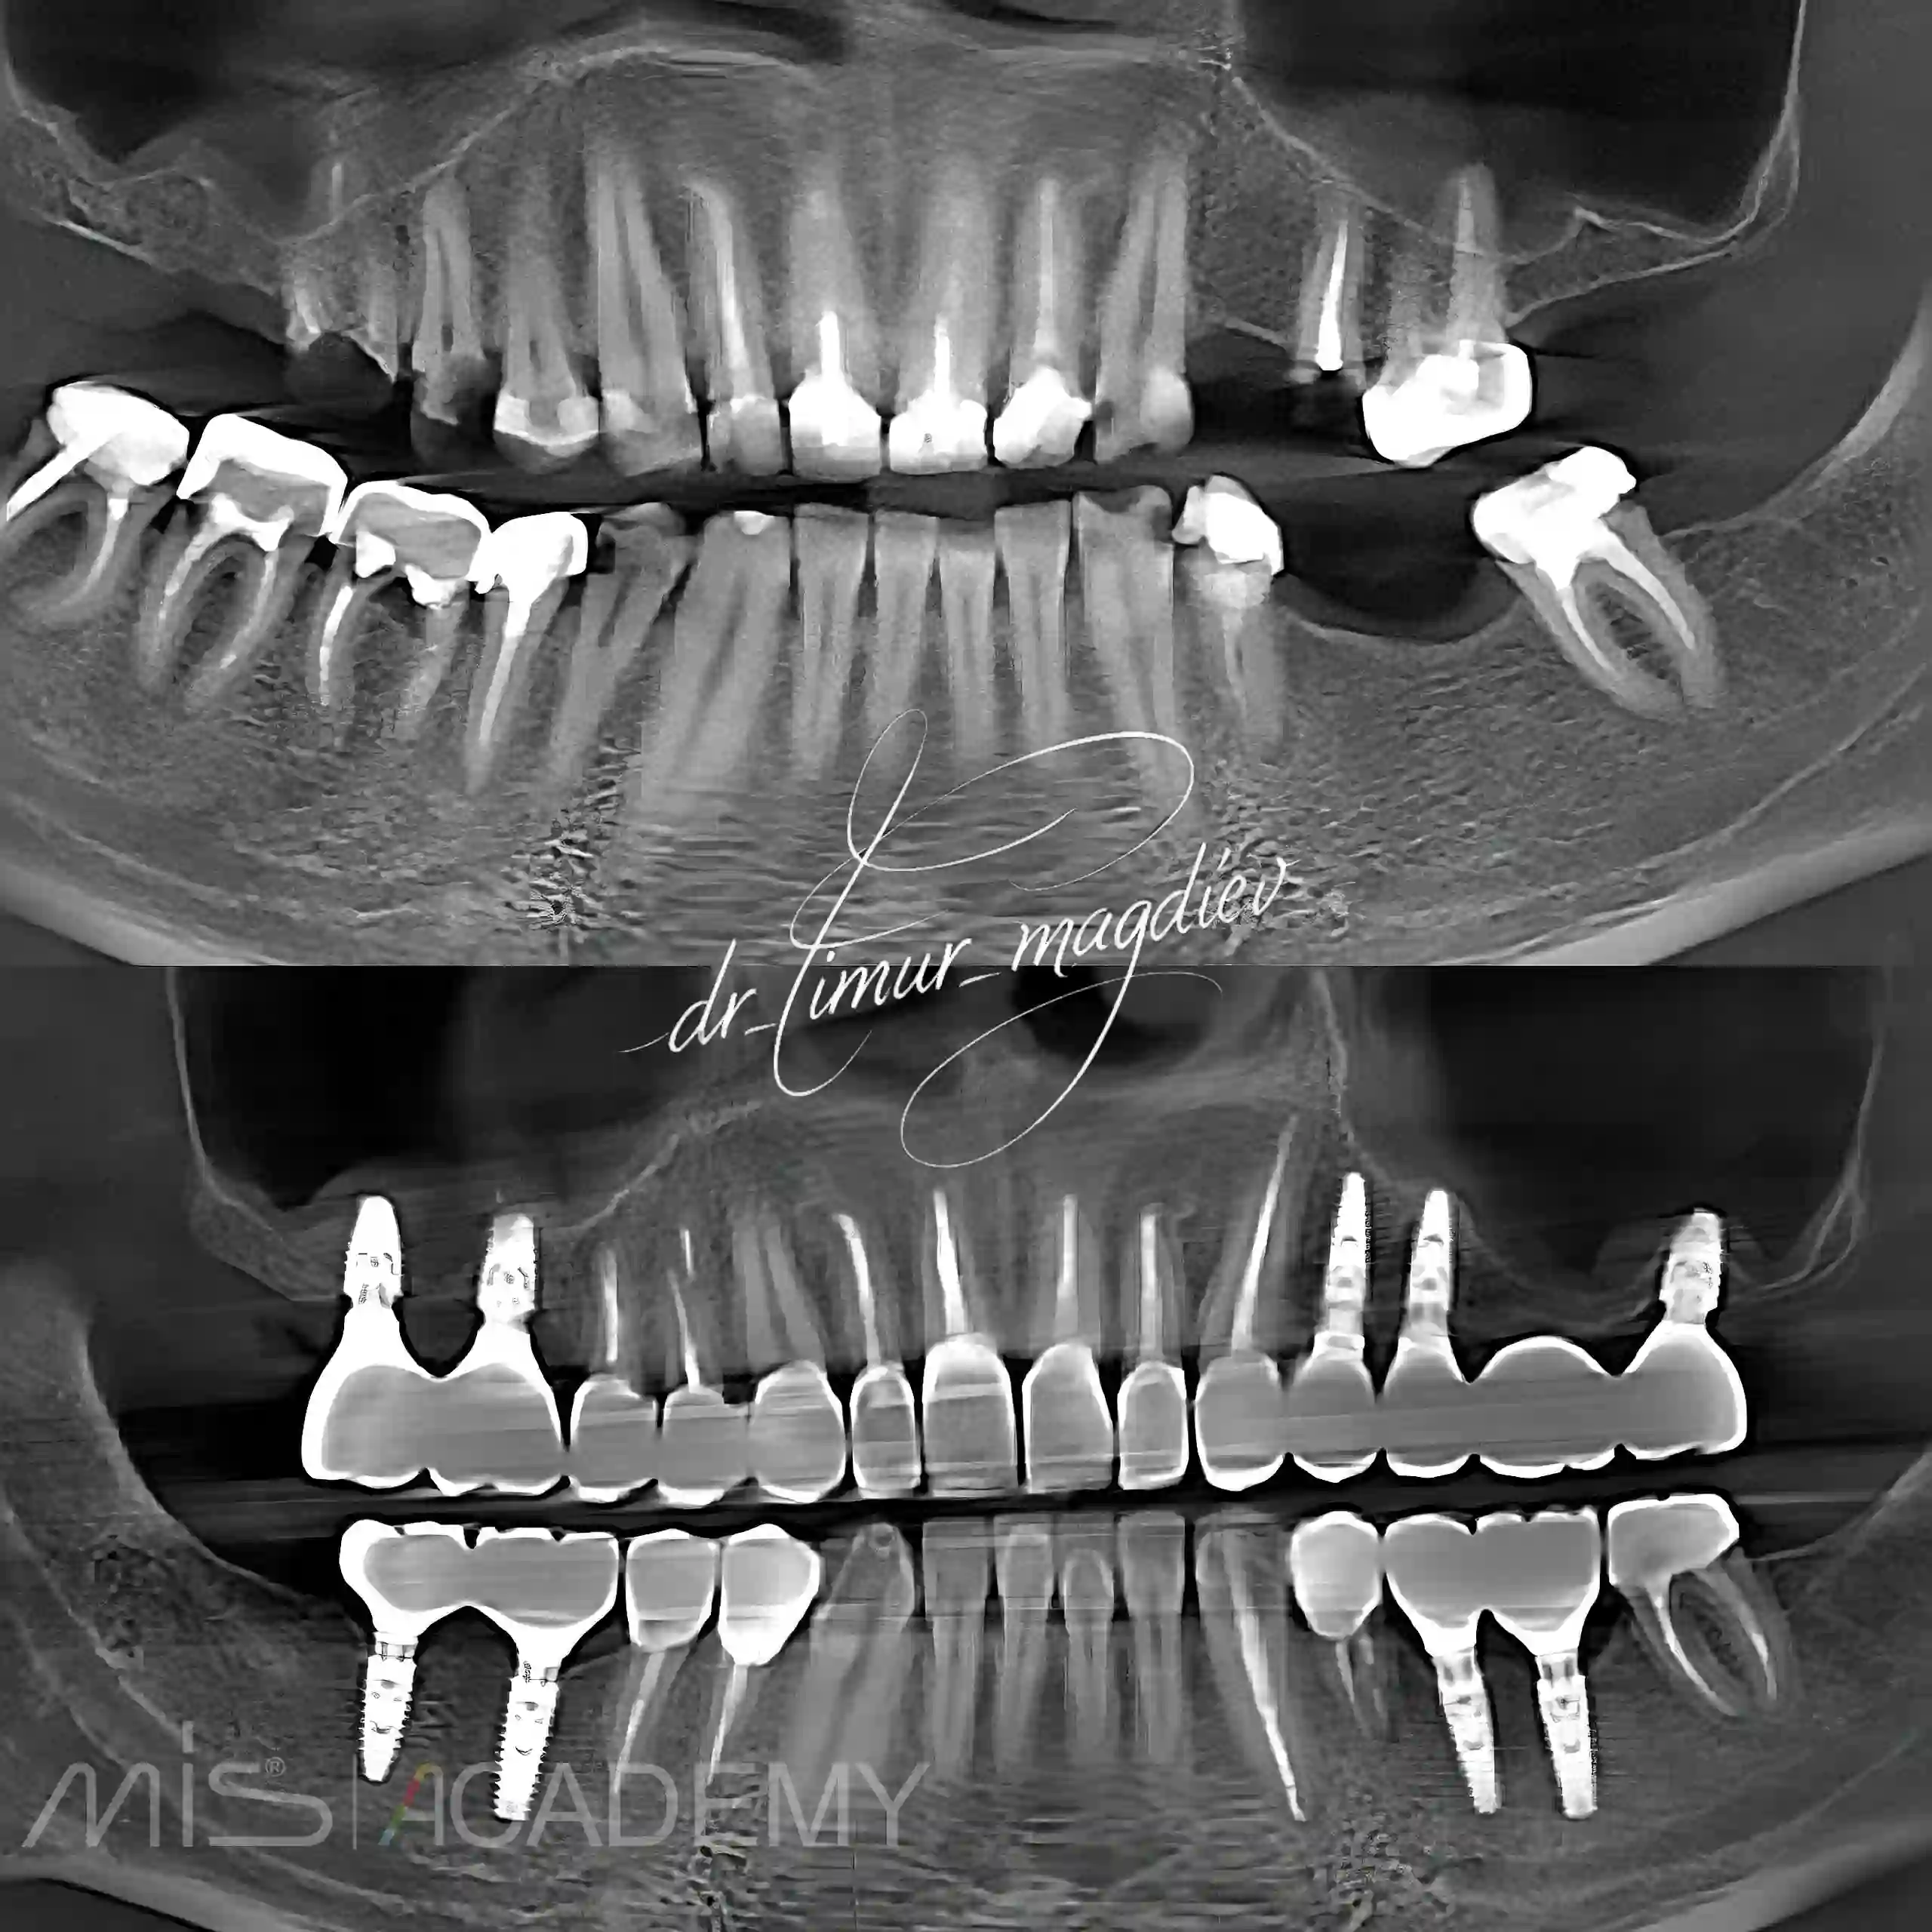

Комплексная реабилитация пациента. От диагностики, сбора дополнительной информации, до окончательного протезирования

— Имплантация MIS C1 + Connect.

— Благодаря навигационной хирургии установили имплантаты без ОСЛ.

— Закрытый кристальный синус.